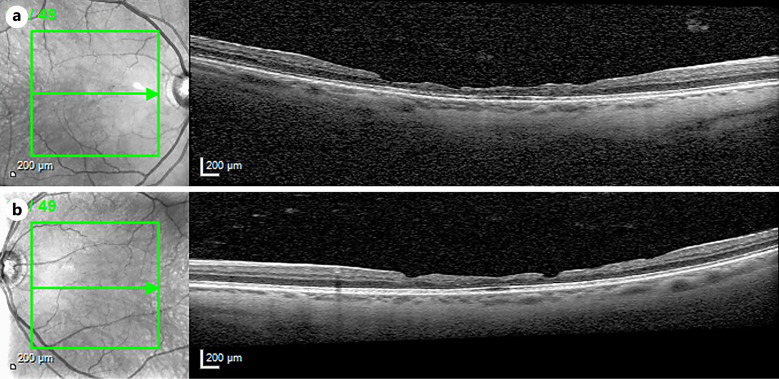

Case presentation: A 53-year-old man with Alport syndrome was referred for gradual decrease in vision. His ocular history was remarkable for intraocular lens implantation secondary to lenticonus in each eye. Fundus photography showed rare white dots in the temporal mid-periphery in each eye and fundus autofluorescence was normal. Optical coherence tomography (OCT) B-scans through the fovea showed irregular thinning of the inner retina with peaks and valleys in the macula of each eye. The ellipsoid zone was intact except for mild patchiness centrally. En face retinal structural OCT angiography (OCTA) images showed a mosaic-like honeycomb pattern in the macular region in both eyes, with hyporeflective depressions in areas of focal retinal atrophy. Retinal OCTA scans showed irregular foveal avascular zone (FAZ) areas with capillaries crossing the FAZ in the left eye, corresponding to islands of preserved retinal tissue. There was predominance of capillaries in the deeper retinal layers centrally.